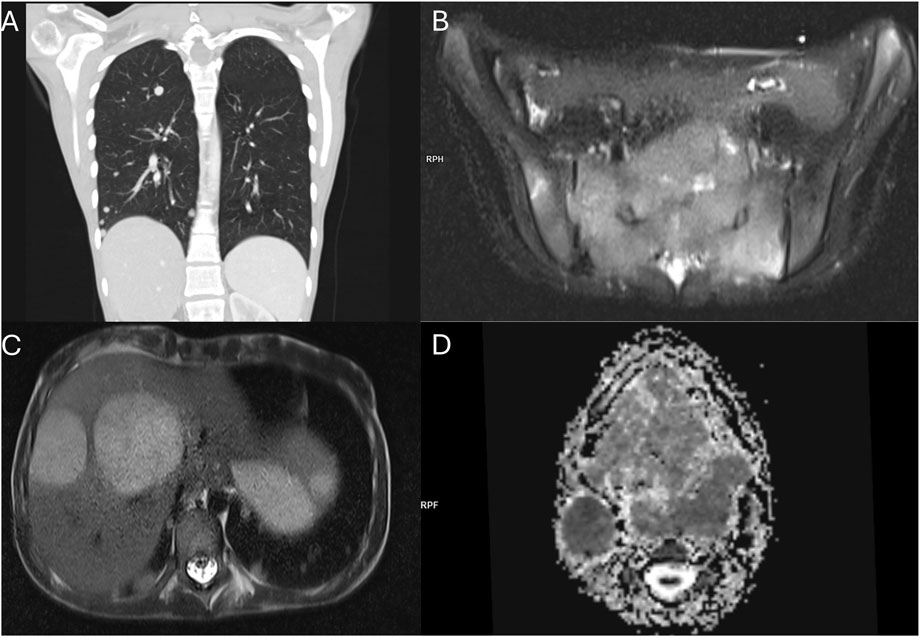

ABSTRACT Introduction Vascular anomalies (VAs), comprising vascular tumors and malformations, are commonly diagnosed based solely on clinical evaluation and imaging. Soft tissue sarcomas (STS) may mimic VAs clinically and radiologically, leading to misdiagnosis, delayed treatment, and suboptimal outcomes. This systematic review aimed to summarize patients with a pathological diagnosis of STS who were initially misdiagnosed with benign VAs, highlighting diagnostic pitfalls. Materials & Methods This systematic review (PROSPERO ID: CRD42024615285) followed PRISMA 2020 guidelines. Inclusion criteria were patients with histologically confirmed STS, initially misdiagnosed as benign VAs based on clinical and/or radiological features. Literature from five databases was reviewed without language or date restrictions. One additional case of alveolar soft part sarcoma initially misdiagnosed and mistreated as an arteriovenous malformation from the authors' institution was added to the analysis. Results The systematic search yielded a total of 96 patients with STS initially misdiagnosed as benign VAs (95 from 77 publications, one own case). Median age at presentation was 6 months (range: newborn–88 years). The most frequent symptom was a swelling or a mass (75%). In most cases, the misdiagnosis was both clinical and radiological. Median diagnostic delay was 5.5 months. Fifty-nine (61.5%) patients received treatment for the misdiagnosed benign VA, including local interventions (51.0%) and systemic therapies (17.7%). The most commonly misdiagnosed STS subtypes were infantile fibrosarcoma, alveolar soft part sarcoma, rhabdomyosarcoma, dermatofibrosarcoma protuberans, angiosarcoma, and Ewing sarcoma. Conclusions Several STS subtypes may mimic benign VAs clinically and radiologically. Misuse of outdated terminology and limited awareness among clinicians contribute to diagnostic delays. To avoid misdiagnoses, the care for patients with benign VAs should be provided by specialists familiar with the classification and natural history of these lesions. In patients diagnosed with benign VAs based on clinical and/or imaging features only, all findings should clearly support the diagnosis. Any ambiguity warrants prompt referral to a tertiary center. A biopsy should be considered in doubtful or atypical cases.